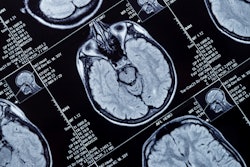

A team at the Medical University of South Carolina (MUSC) is working on testing a portable MRI scanner from Hyperfine to perform scans on stroke patients while they are being transported in a moving ambulance.

The Hyperfine scanner weighs about 1,400 lb and is about the size of an office printer turned on its side. Researchers touted MRI's ability to provide accurate imaging of small blockages and blood clots in stroke patients without exposing patients or staff to radiation. They said using MRI in ambulances could especially help patients being transported from rural settings.

By performing MRI en route to hospitals, MUSC hopes to reduce the number of stroke deaths. The team will write up a report of their practical demonstration.